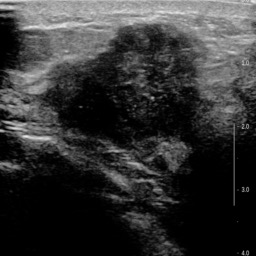

Ultrasonography is an important routine examination for breast cancer diagnosis, due to its non-invasive, radiation-free and low-cost properties. However, it is still not the first-line screening test for breast cancer due to its inherent limitations. It would be a tremendous success if we can precisely diagnose breast cancer by breast ultrasound images (BUS). Many learning-based computer-aided diagnostic methods have been proposed to achieve breast cancer diagnosis/lesion classification. However, most of them require a pre-define ROI and then classify the lesion inside the ROI. Conventional classification backbones, such as VGG16 and ResNet50, can achieve promising classification results with no ROI requirement. But these models lack interpretability, thus restricting their use in clinical practice. In this study, we propose a novel ROI-free model for breast cancer diagnosis in ultrasound images with interpretable feature representations. We leverage the anatomical prior knowledge that malignant and benign tumors have different spatial relationships between different tissue layers, and propose a HoVer-Transformer to formulate this prior knowledge. The proposed HoVer-Trans block extracts the inter- and intra-layer spatial information horizontally and vertically. We conduct and release an open dataset GDPH&GYFYY for breast cancer diagnosis in BUS. The proposed model is evaluated in three datasets by comparing with four CNN-based models and two vision transformer models via a five-fold cross validation. It achieves state-of-the-art classification performance with the best model interpretability.

翻译:超声波分析是乳腺癌诊断的一个重要常规检查,原因是其非侵入性、无辐射和低成本的特性。然而,由于其内在局限性,它仍不是乳腺癌的第一线筛选测试。如果我们能够精确地通过乳房超声图像诊断乳腺癌(BUS),它将是一个巨大的成功。我们提出了许多基于学习的计算机辅助诊断方法,以实现乳腺癌诊断/感官分类。然而,其中多数方法需要事先确定性能模型,然后对ROI内部的跨值进行分类。常规分类支柱,如VGG16和ResNet50等,可以在没有ROI要求的情况下实现有希望的分类结果。但是这些模型缺乏可解释性,从而限制了其在临床实践中的使用。在本研究中,我们提出了一个新的无乳腺癌诊断模型,在超声波图像中进行解释性特征描述。我们利用了先前的解剖学学学知识,即恶性肿瘤和良性肿瘤模型在不同组织层之间有着不同的空间关系,并提议采用状态解析法来编制这一先前的知识。拟议中的HOVer-Trans-Trading-Tradef-trainal Ex-deal-dealal-deal-deal-deal-degraphal-deal-deal-deal-deal-deal-deal disal disal-dal-dal-dal-dal-dal-deal-deal-dal-deal-deal-deal-dal-dal-dal-dal-dal-dal-dal-dal-dal-dal-dal-dal-dal-dal-I-dal-Iversal-dal-Ial-d-d-I-d-d-I-I-I-I-I-I-I-I-I-I-I-I-I-I-I-I-I-I-I-I-I-I-I-I-I-Ial-I-Ial-Ial-I-I-I-I-I-I-I-I-I-I-I-I-I-I-I-I-I-I-I-I-I-I-I-I-I-I-I-I-I-I-I-I-